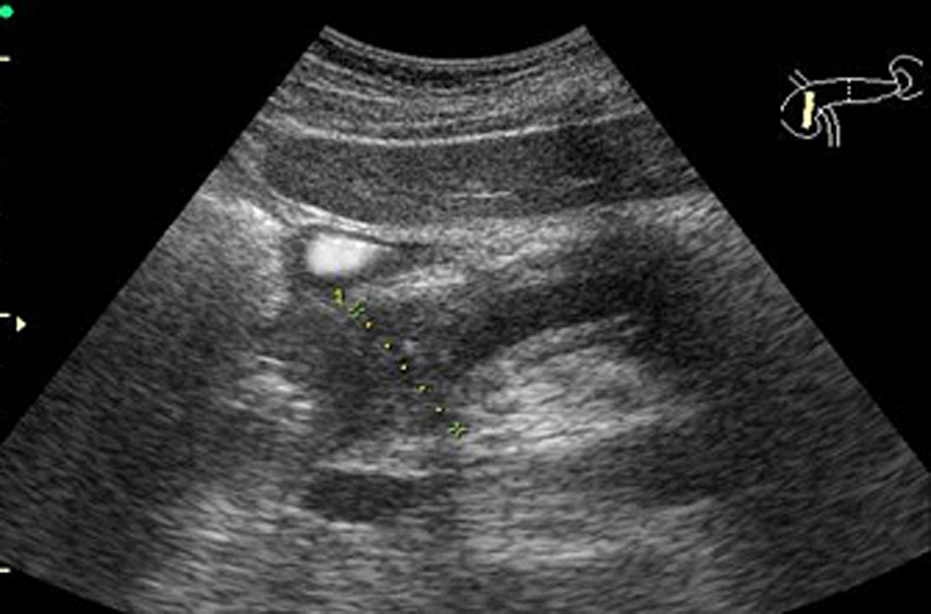

Рис. 07. Ультразвуковое изображение кистозного образования в правой доле печени с указанием определения глубины прокола при пункции кисты печени.

Как правило, игла выбирается большей длины, чем получено при измерении, поскольку есть необходимость не только достижения кончиком иглы образования, но и проникновение внутрь на достаточную глубину. Кроме того, в силу эластичности тканей, пунктируемое образование может смещаться, что ещё дополнительно увеличивает расстояние для доступа.